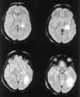

Multifocal intracranial lesions

A seizure, formally known as an epileptic seizure, is a period of symptoms due to abnormally excessive or synchronous neuronal activity in the brain. Outward effects vary from uncontrolled shaking movements involving much of the body with loss of consciousness (tonic-clonic seizure), to shaking movements involving only part of the body with variable levels of consciousness (focal seizure), to a subtle momentary loss of awareness (absence seizure). [Source: Wikipedia ]